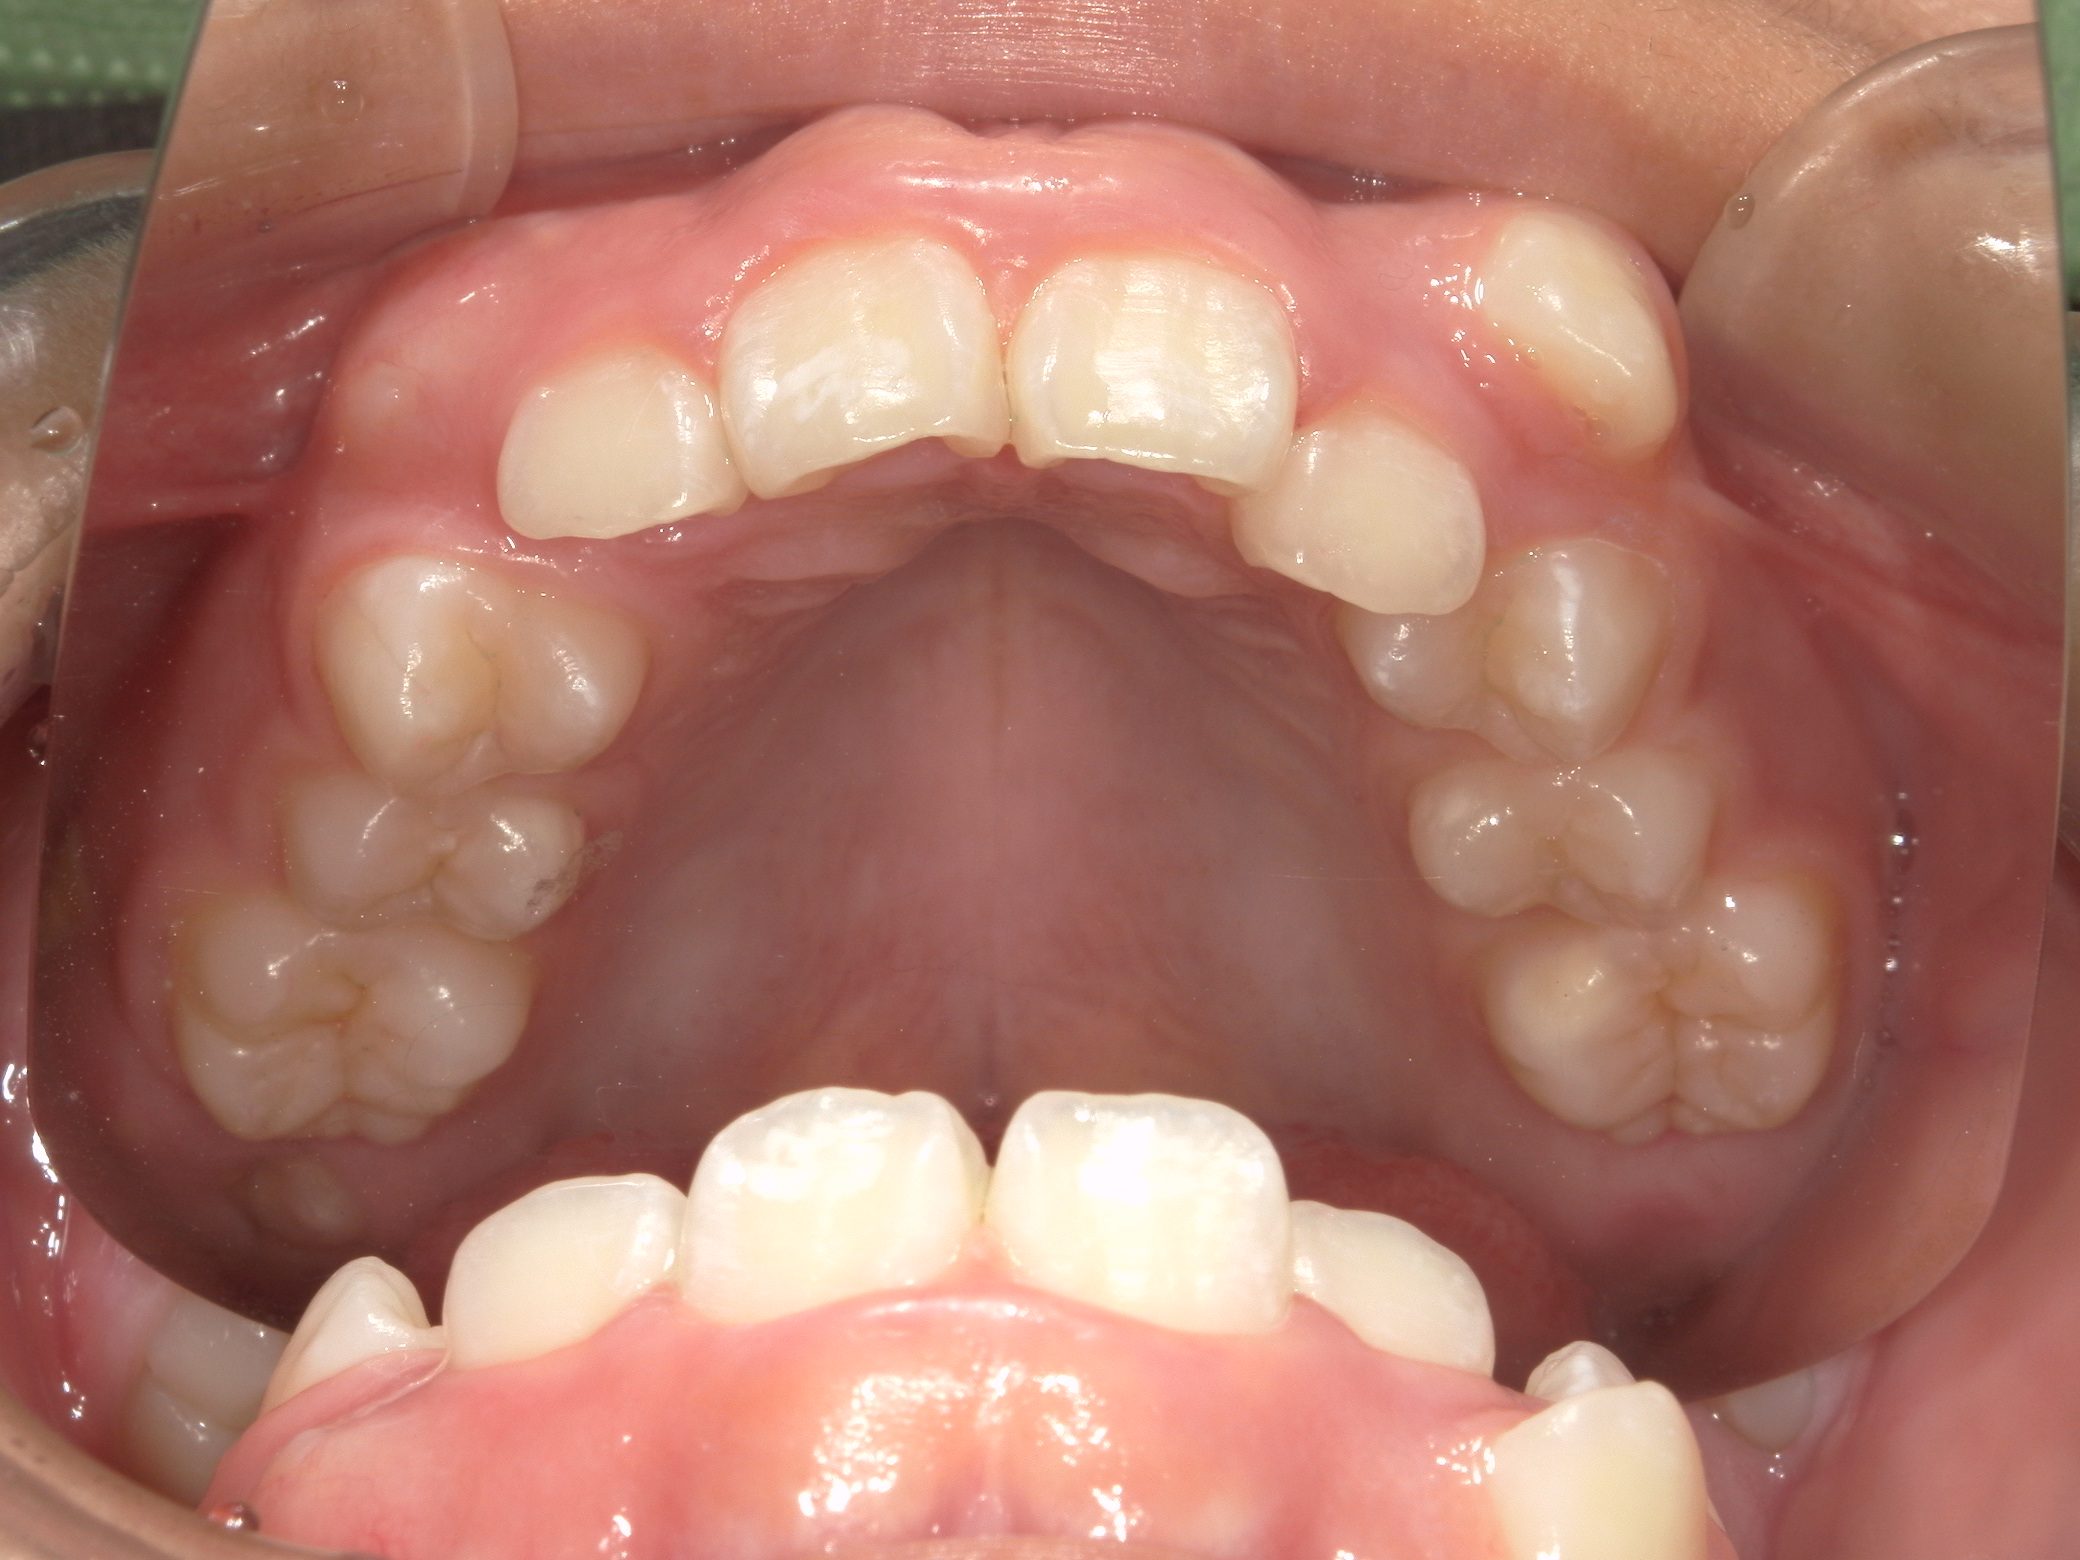

【小学生】インビザラインフル 叢生(でこぼこ)と 上顎前突(出っ歯)を改善

Before

After

八重歯と上顎前突(出っ歯傾向)が気になるということで来院

上下4本の歯を抜歯して矯正しました

しっかり装着してくれたので3年はかかると予測していましたが、1年半で終了しました

咬み合わせも改善し満足してくれました